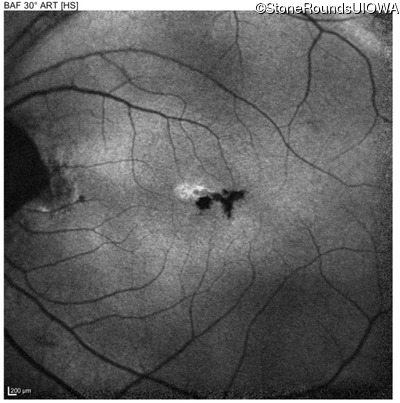

Blue Autofluorescence - Left - 20/40 +1

Exemplar